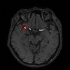

EIRL Brain Aneurysm(エイル・ブレイン・アニュリズム)検出画面(エルピクセル提供)